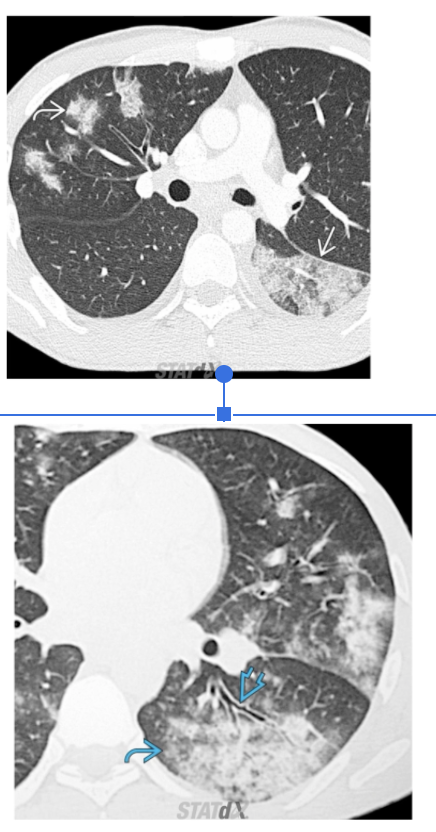

A

Cavitary lesion with air fluid level (The air rises above the fluid and there is a flat surface at the "air-fluid" interface)